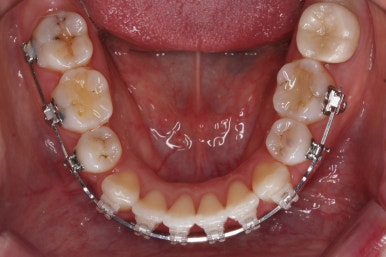

입안 모습입니다.

윗니와 아랫니 모두 각각 보면 가지런해 보이며 발치를 했던 자리도 거의 다 메워져서 양호해 보입니다. 훑어 보면 굳이 더 교정을 해야할 부분이 있을까? 싶겠지만 다음 사진을 보면 알 수 있습니다.

우선 재배열 부터 하였습니다.

브라켓의 위치가 교정을 하는데 있어서 매우 중요하기에 일부분은 먼저 재부착을 하였습니다.